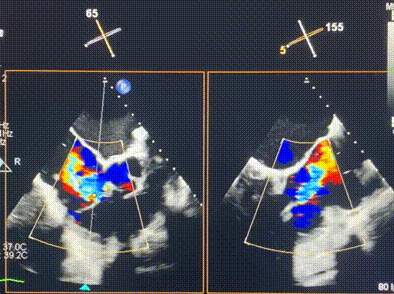

術前超聲提示重度三尖瓣反流

術中輸送器在超聲引導下調整位置